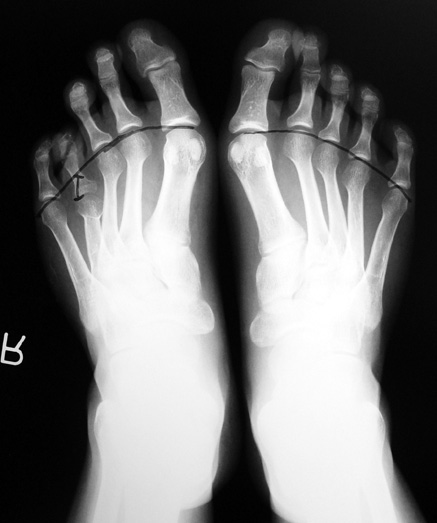

Vaka 2